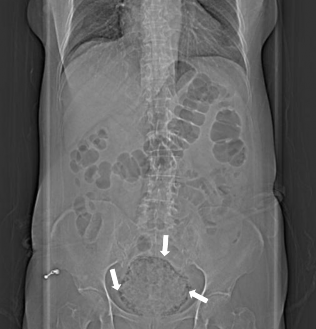

Imaging examination is indispensable in the diagnosis of EC, and plain abdominal radiography is the most common method. Studies have revealed that plain abdominal radiography accounts for 84% of reported cases.[2] The representative radiographic findings present a radiolucent curvilinear air around the bladder wall (Figure 3). The presence of gas in the bladder wall is characterized by pebbles or “bead necklace” appearance, reflecting irregular thickening of the non-dependent mucosal surface due to submucosal blebs.[16] CT is needed for a definite diagnosis, and shows the severity and extent of EC.[16] CT can also be used to identify infections that are not obvious on plain abdominal radiography.[17,18] More importantly, CT can distinguish between other diseases that can interfere, such as vesicocolic or vesicovaginal fistula, adjacent neoplastic disease, trauma, pneumatosis cystoides intestinalis, vaginitis emphysematosa, and gas gangrene of the uterus.[16,19,20] Ultrasound can display wall thickening and hyperechoic region dirty acoustic shadowing,[21] but some authors report that it has a low sensitivity.[22] Cystoscopy is not necessary for the diagnosis, because other examinations, such as IVU, ultrasound, or cystography are needed for confirmation.[23]

Figure 3: X-ray of kidney, ureter, and bladder reveals air (white arrows) existed in the bladder wall and bladder cavity.